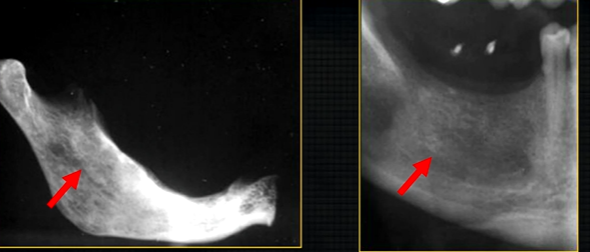

oblique lateral technique allows you to take extraoral radiographs

image receptor is placed outside the mouth and against the side of the face

resultant radiographs are larger and show anatomical structures in both jaws

direction of Xray beam on this skull

for right hand side - tube head left and receptor opposite - passes between the cervical spine and the left ascending ramus of the mandible - viewed like you are looking at the patient’s right cheek

posterior edge of left side

radiolucent band around the posterior part of the body of the mandible

created by inferior dental nerve and blood vessel, created by the inferior dental canal

the edges of the canal can be seen as thin, white radiopaque lines → ‘tram lines’

inferior dental canal can easily be seen in cross sectional dental images